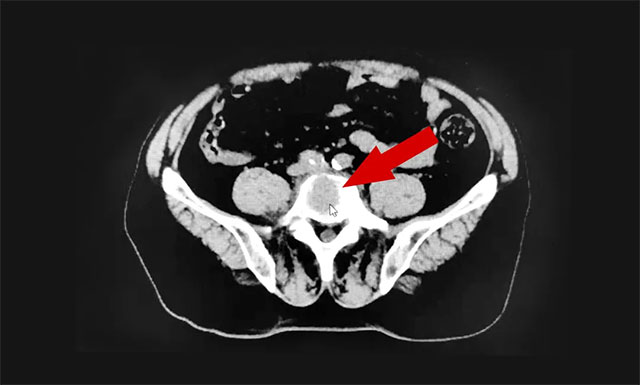

▲ 患者腰椎部出现转移性骨肿瘤